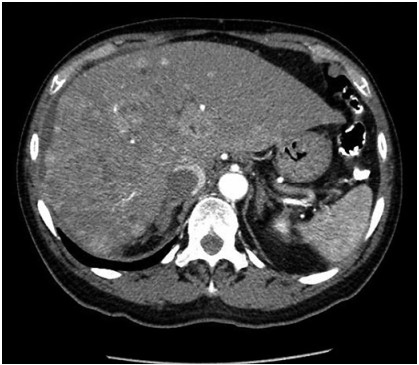

Abstract: Leiomyosarcomas (LMSs) are extremely rare and comprise only 1.2% of small bowel malignancies. Advancements in immunohistochemical techniques have allowed for the differentiation between LMSs and gastrointestinal stromal tumors. LMSs remain difficult to detect via endoscopy and require a more intricate diagnostic approach. The staging and sizing of these tumors are important prognostic indicators. We report a case of a 67-year-old male who presented with bulging lower extremity veins, abdominal bloating, and weight loss. A CT of the abdomen and pelvis revealed a pelvic mass arising from the small bowel and a metastatic hepatic lesion, which was found to be compressing the inferior vena cava. A biopsy of the hepatic lesion confirmed the diagnosis of metastatic LMS.